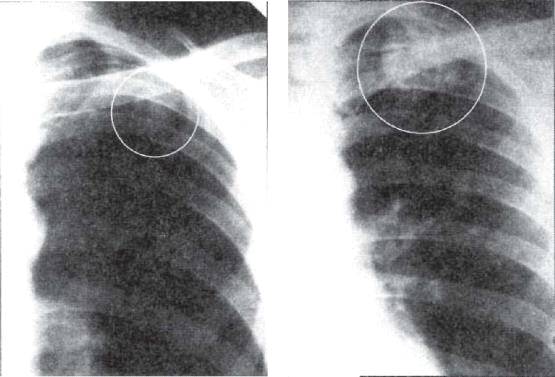

а б

Рис. 11.4. Бронхолобулярный инфильтрат во II сегменте правого легкого.

а - фрагмент рентгенограммы легких; б - фрагмент продольной томограммы в прямой проекции.

Бронхолобулярный инфильтрат обычно

характеризуется наличием в кортикальной зоне легочного поля, чаще в I,

II или IV

сегментах, ограниченного затемнения (фокусной тени) в основном малой

интенсивности, диаметром до 3 см. Инфильтрат имеет полигональную форму,

вытянутую по направлению к корню легкого, и размытые наружные контуры (рис.

11.4). КТ-исследование позволяет выявить просвет и деление мелкого бронха,

вокруг которого сформировался инфильтрат (рис. 11.5). Просвет бронха иногда

заполнен плотными казеозными массами. На томограмме бронхолобулярный инфильтрат

нередко выглядит как конгломерат из нескольких более или менее плотных мелких

очагов, объединенных зоной перифокального воспаления.